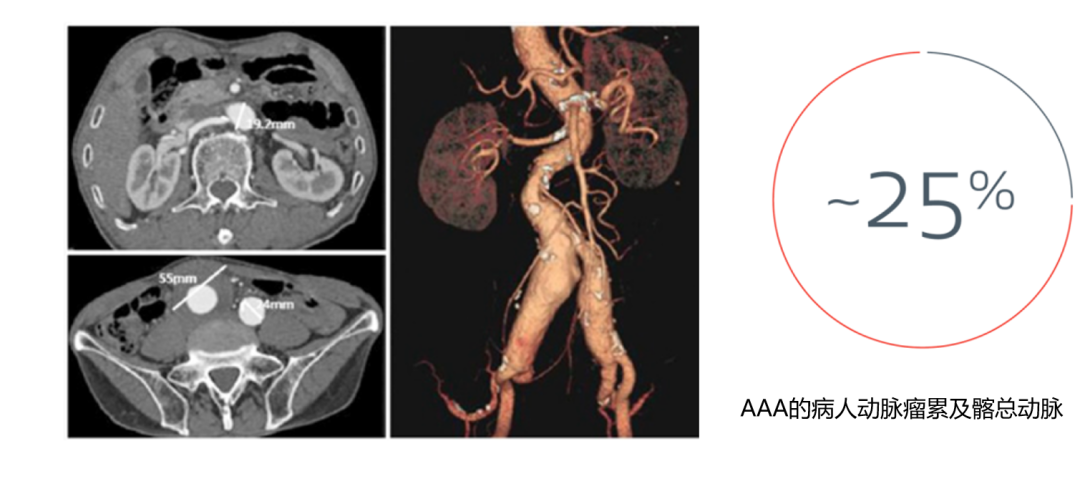

★ 流行病学数据

约25%的腹主动脉瘤(AAA)患者合并髂总动脉受累 ,且动脉瘤直径≥55mm时 ,髂动脉受累风险显著增加。临床实践中 ,忽视髂内动脉保留可能导致严重后果 ,如90岁患者因髂内动脉栓塞术后死亡的案例 ,警示需重视髂内动脉保护。